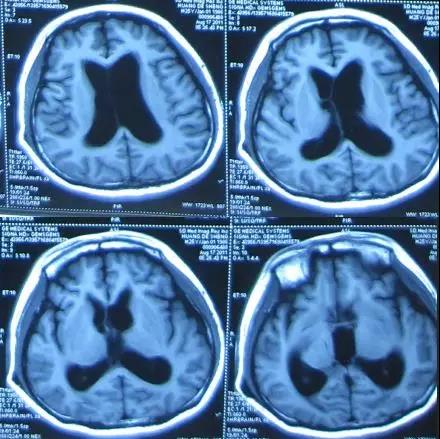

头部CT(外院2011年10月3日)示V-P分流术后,右侧额叶及左侧顶叶见片状低密度影;第三脑室、双侧脑室扩张;中线略向右移位(图-6)。

图-6:2011年10月3日头部CT

住院治疗第3天即2011年10月8日,按计划进行原V-P分流管拔除术和侧脑室外引流术,术前例行检查头部CT:脑室缩小(图-7)。因患者侧脑室无明显扩张,为避免放置外引流困难,予临时保留侧脑室端,留取脑脊液进行细菌培养。

图-7:2011年10月8日头部CT